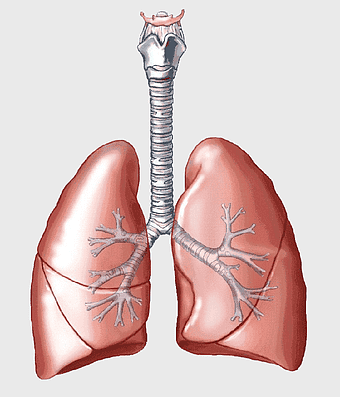

lungs illustration, respiratory system diagram, human lungs anatomy, pulmonary alveolus structure, bronchial tree visualization, trachea and bronchi, lung lobes detail -

human lungs icon, monochrome lung illustration, breathing organ diagram, anatomy line art, pulmonary tree structure, respiratory system graphic, black and white organ depiction -